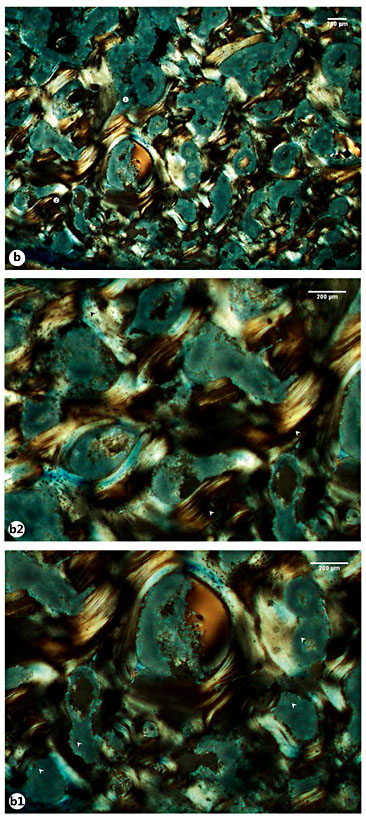

A remodeled callus microstructure characterized by well-defined osteons and interstitial lamellae was also identified in the right rib sample retrieved from Sk. 1,196. In this sample, multiple bays of bone resorption were observed in the endosteal and periosteal surfaces. At some points, larger areas of bone resorption enclosed by thin layers of bone lamellae were seen, in addition to enlarged Haversian canals and numerous osteocyte lacunae (fig. 7a-d). In contrast with the above-mentioned case, the sample retrieved from the right radius of the same Sk. 1,196 individual showed a more immature microstructure. For example, an intricate network of trabeculae, some of them with signs of bone resorption, was observed in the posterior side of the bone callus. The typical structure of a mature cortical tissue was recorded as absent from the core of the bone callus, as well as from the opposite anterior surface. That is, no clearly defined osteons, interstitial lamellae, and Haversian canals were observed. Instead, the anterior portion appeared to be formed by horizons of lamellar bone pinpointed by a high density of osteocyte lacunae, which suggests distinct levels of bone deposition. Irregular lines running alongside the bone lamellae were also seen. Finally, a pattern of disorganized lamellae and immature bone populated by osteocyte lacunae and separated by irregular areas of bone resorption and discrete Haversian canals was seen in the interface between the anterior and the posterior surfaces of the bone callus (fig. 8a-e1). The most striking example of an immature callus microstructure came from the Sk. 198 sample. In spite of the healed macroscopic appearance, the histological study revealed a cortical tissue formed by an intricate system of lamellae, comparable to trabeculae, in which multiple branches and islands of well-preserved lamellae connecting partially digested osteons were observed. A combination of mature lamellae with more immature bone populated by multiple osteocyte lacunae and large resorption spaces was also noticed. At the periosteal level, a rim of lamellae in distinct stages of maturation was seen bordering the outer surface of the bone (fig. 9a-d).

a Microscopic view of the Sk. 198 right fibula callus showing the cortical tissue formed by a disorganized net of bone lamellae and remnants of ancient Haversian systems (circle 1 and 2). a1, a2 Details of the previous image showing large bays of bone resorption being formed after digestion of previous osteons (white arrowheads). b Another view highlighting numerous areas of bone resorption. b1 Magnification of the previous image revealing the large and irregular areas of bone resorption (white arrowheads). b2 Another magnification showing mature (white arrowheads) and more recently formed lamellae with osteocyte lacunae (black arrowheads). c Bone segment combining densely packed lamellae on the bone surface (black arrowheads) and branches of disorganized lamellae with osteocyte lacunae in the innermost areas of the cortical bone (white star). d Another view showing the outer surface composed of lamellae with a haphazard arrangement (white star) and pinpointed by numerous osteocyte lacunae. Polarized light. Magnification ×40; ×100.

a Microscopic view of the Sk. 198 right fibula callus showing the cortical tissue formed by a disorganized net of bone lamellae and remnants of ancient Haversian systems (circle 1 and 2). a1, a2 Details of the previous image showing large bays of bone resorption being formed after digestion of previous osteons (white arrowheads). b Another view highlighting numerous areas of bone resorption. b1 Magnification of the previous image revealing the large and irregular areas of bone resorption (white arrowheads). b2 Another magnification showing mature (white arrowheads) and more recently formed lamellae with osteocyte lacunae (black arrowheads). c Bone segment combining densely packed lamellae on the bone surface (black arrowheads) and branches of disorganized lamellae with osteocyte lacunae in the innermost areas of the cortical bone (white star). d Another view showing the outer surface composed of lamellae with a haphazard arrangement (white star) and pinpointed by numerous osteocyte lacunae. Polarized light. Magnification ×40; ×100.

With regard to the Sk. 198 right fibula callus, the mesh-like pattern observed seems to mirror the last phases of the reparative stage. The remodeling phase is the longest (it may require 6-9 years in adults) and aims to reestablish the skeletal integrity [50,51]. The reparative phase is characterized by the development of an organized fibrous mass [52] in a process that recapitulates the embryonic intramembranous and endochondral ossifications [53,54,55]. This soft or fibrous callus will bond the broken ends [24] and guarantee the mechanical stability of the injured area [56]. Other local changes include mineralization [50], degradation of the nonmineralized matrix, and the formation of new trabeculae, which compounds the primary bony callus [24]. In the study of bone callus morphogenesis, Gerstenfeld et al. [57] showed that during the endochondral process of fracture healing, the cortex and cartilage undergo resorption, being replaced by an inner supporting network of trabeculae that will stabilize the fracture. Ayoub et al. [58] also observed a characteristic histological picture characterized by islands of newly built bone surrounded by cartilage and interspersed, at some points, by lamellar bone. The reparative stage may last several weeks. In some cases, the bony callus may originate as early as the first week after injury [59]. Analyzing the morphology of mineralized bone calluses, Liu et al. [60] noticed that a microstructure composed of poorly organized tissue (woven bone) and well-aligned lamellae develops during the 2-9 weeks of healing.